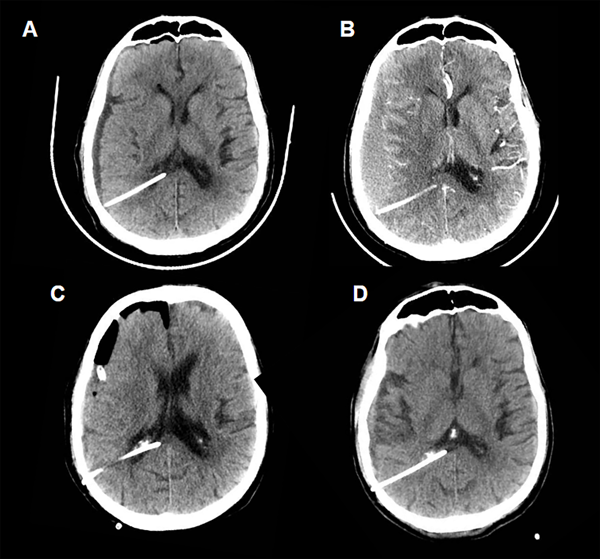

Caso 1 (Fig. 3)

Paciente masculino de 75 años de edad, que consulta por mareos, inestabilidad en la marcha e incontinencia urinaria. Se realizó RMN y TC donde se evidencia voluminoso meningioma petroclival izquierdo asociado a hidrocefalia obstructiva. Se decidió colocar una VDVP Codman Certas(R) a 150 mmH20. En la TC de cerebro control a las 48 hs postoperatorias se evidenciaba pequeño higroma derecho por lo que se aumenta la presión valvular a 170 mmH20 (Fig. 3A). Mantuvo controles periódicos, con crecimiento progresivo de dicha colección y aumento de la presión valvular hasta 200 mmH20. A los 2 meses postoperatorios, en contexto de crisis convulsiva, se realizó nueva imagen donde se constata el desarrollo de un voluminoso hematoma subdural (Fig. 3B). Se realizó la evacuación quirúrgica del mismo sin intercurrencias (Fig 3C). El paciente actualmente presenta estabilidad clínica e imagenológica, manteniendo la presión valvular en 200 mmH20, con un seguimiento sin nuevas intercurrencias de 19 meses (Fig. 3D).

Figura 3. Caso 1.

Fig A. Tomografía de cerebro control realizada a las 48 hs postoperatorias. Por evidencia de higroma se aumenta la presión valvular de 150 mmH20 a 170 mmH20, con posterior egreso sanatorial. Fig. B. TC de cerebro a los 2 meses postoperatorios, donde se evidencia hematoma subdural frontoparietal derecho subagudo (VDVP a 200 mmH20). Fig. C. Control realizado en el postoperatorio inmediato de la evacuación de dicho hematoma, se evidencia cavidad quirúrgica con drenaje subdural. Fig. D. Tomografía realizada al último control, sin signos de complicaciones.